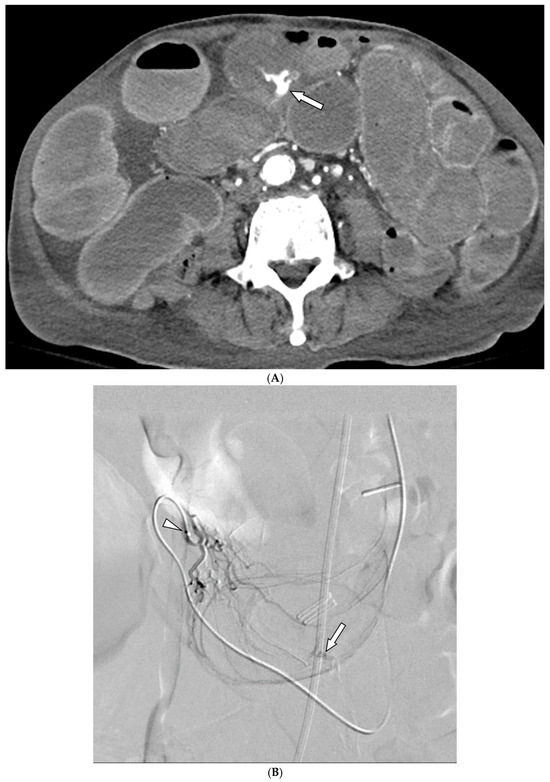

Embolization with Quick-Soluble Gelatin Sponge Particles for Lower Gastrointestinal Bleeding: A Multicenter Study

by Chang Ho Jeon, Seung Boo Yang, Woo Jin Yang, Ji Hoon Shin, Kyu-Pyo Kim, Jung-Hoon Park and Jin-Hyoung Kim

Medicina 2025, 61(11), 1964; https://doi.org/10.3390/medicina61111964 - 31 Oct 2025

Background and Objectives: Transarterial embolization (TAE) serves as a valuable alternative for gastrointestinal bleeding when endoscopy fails or is inaccessible. Quick-soluble gelatin sponge particles (QS-GSPs) dissolve rapidly and may reduce ischemic complications compared to permanent embolic agents. This study evaluated the safety and [...] Read more.

Background and Objectives: Transarterial embolization (TAE) serves as a valuable alternative for gastrointestinal bleeding when endoscopy fails or is inaccessible. Quick-soluble gelatin sponge particles (QS-GSPs) dissolve rapidly and may reduce ischemic complications compared to permanent embolic agents. This study evaluated the safety and effectiveness of TAE using QS-GSPs for acute lower gastrointestinal bleeding. Materials and Methods: This retrospective multicenter study analyzed patients who underwent TAE with QS-GSPs for acute nonvariceal lower GI bleeding between 2021 and 2024. Technical success (occlusion or stasis of blood flow in the target artery), clinical success (cessation of bleeding symptoms with hemodynamic stability during the week following TAE without major complications), and procedure-related complications were assessed. Results: A total of 29 patients (mean age 64.9 years) were included. Active bleeding was detected in 6 patients (20.7%) on angiography. Embolized arteries included jejunal (n = 7), ileal (n = 7), ileocolic anastomotic (n = 1), cecal (n = 2), colic (n = 7), and rectosigmoid (n = 5) arteries. QS-GSPs (150–350 μm (n = 10) or 350–560 μm (n = 19)), which dissolve completely within several hours, were used as the sole embolic agents. Technical and clinical success rates were 100% and 75.9% (22/29), respectively. Clinical failure occurred in seven patients (24.1%) due to persistent (n = 4) or recurrent (n = 3) bleeding within one week. Transient bowel ischemia occurred in two patients (6.9%) but resolved spontaneously. The clinical success rate did not differ significantly between patients with active bleeding (66.7%) versus those without (73.9%). Conclusions: TAE with QS-GSPs for acute lower GI bleeding demonstrated a favorable safety profile with clinical success exceeding 75%. Transient bowel ischemia occurred in 6.9% of patients with spontaneous resolution, and no bowel infarction was observed. Full article

Show Figures

Figure 1